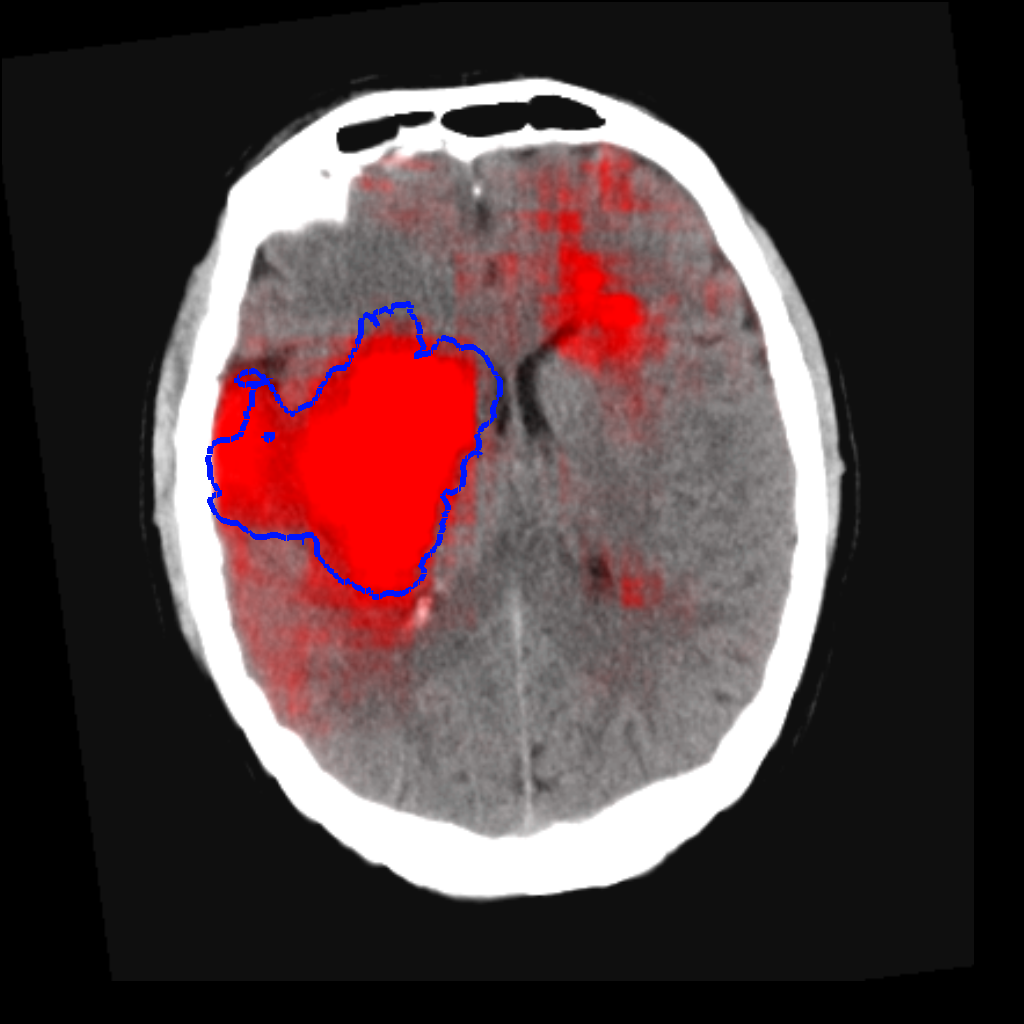

Fig. 3 shows a scatter plot and a Bland-Altman plot of the true and predicted volumes for all subjects in the testing folds using the proposed method. The mean volume error is -2.8 ml (the prediction is a slight underestimation) and the mean absolute volume error is 36.7 ml. The mean Dice score is 0.48. A representative set of predictions is shown in Fig. 4.